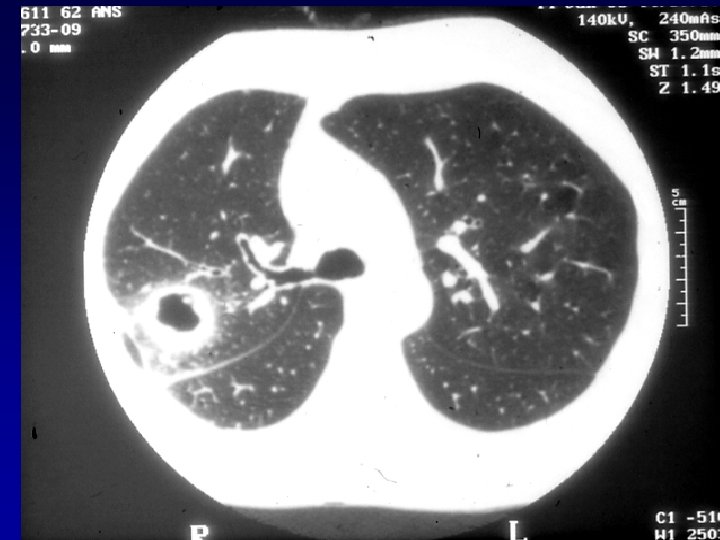

Radiologie: • Radiographies: – Poumons: • WG: Infiltrats interstitiels ou alvéolaires, parfois evanescents Nodules pouvant devenir cavitaires 34% des patients: infiltrats/nodules asymptomatiques • CSS: Infiltrats (surtout) evanescents chez 38 -70% Nodules: moins fréquents, moins tendance à cavitation Hémorragie alvéolaire: rare • PAM: Infiltrats alvéolointerstitiels 70%